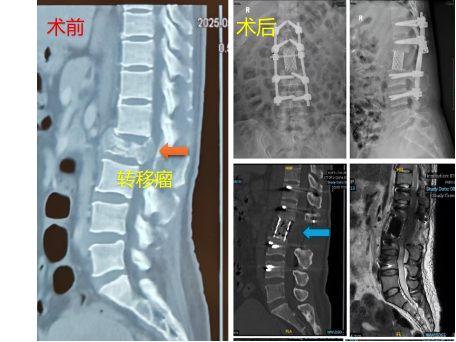

患者三、膀胱癌腰椎脊柱转移行肿瘤全切除+椎体重建内固定术

患者因膀胱癌腰椎脊柱转移,双下肢急性瘫痪大小便失禁,急诊椎体肿瘤切除+椎体重建内固定术。